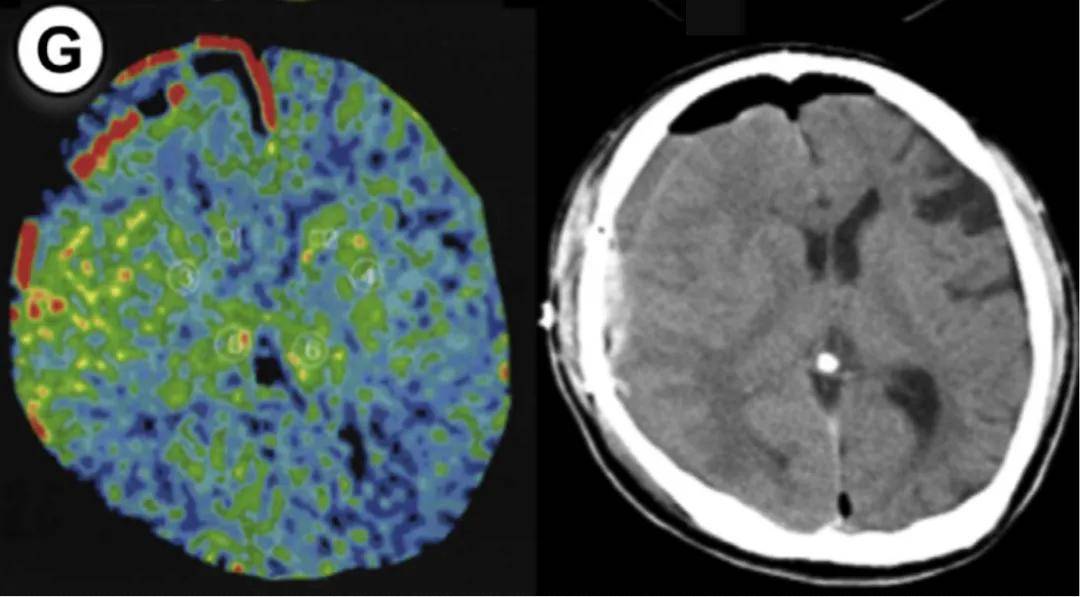

病例1:55岁男性,右侧大脑手术。方法1 rCBF增加率47%,方法2达55%(超过50%阈值)。术后第3天未维持镇静,第2天发生脑出血,改良Rankin量表评分恶化。

病例2:55岁男性,左侧大脑手术。方法1和方法2的rCBF增加率均为50%,达到预警阈值。术后第1天发现少量蛛网膜下腔出血(SAH),因术前规划2天镇静和血压控制,未出现神经功能缺损。

病例3:44岁女性,左侧大脑手术。方法1 rCBF增加率100%,方法2达114%,术后第2天脑出血。因术后及时给予1天镇静和严格控压,未遗留神经功能问题。

病例4:49岁女性,右侧大脑手术。方法1 rCBF增加率89%,方法2达133%,术后第5天发现硬膜下血肿合并蛛网膜下腔出血。

病例5:49岁男性,左侧大脑手术。方法1 rCBF增加率78%,方法2高达149%,术后第2天发现少量蛛网膜下腔出血。术后给予1天持续镇静,出血未扩大。

病例6:26岁男性,右侧大脑手术。方法1 rCBF增加率63%,方法2达72%,术后第2天发现硬膜下血肿合并蛛网膜下腔出血。术后1天镇静干预后出血吸收。

病例7:35岁女性,左侧大脑手术。方法1 rCBF增加率77%,方法2达67%,术后第2天发现出血合并脑室内出血。因术前知晓rCBF超标,提前规划镇静干预。

7个病例年龄范围25-55岁(无儿童),出血类型包括脑出血(ICH)、蛛网膜下腔出血(SAH)、硬膜下血肿(SDH)及混合出血,发病时间术后1-5天。所有患者rCBF增加率均≥30%(方法1)或≥50%(方法2),证实这两个阈值的预警价值。